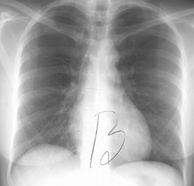

| Prior imaging | oldest & most recent |

| Technical quality | Rotation (spinous processes equidistant from medial end of clavicles)

Inspiration (6 - 7 anterior ribs in MCL) Penetration (spinous processes visible) |

| Lines, tubes | ETT: 5 cm sup to carina [just sup to arch] [has excursion +/- 2 cm] Trachoeostomy tube tip: 1/2 to 2/3 from stoma to carina CVC: SVC (if RA → may arryth or perforatn) S-G: < 2 cm lat to hila NGT: > 10 cm w/n stomach FT: lig of Trietz

| Abdomen | Diaphragm, pneumoperitoneum, colonic interposition, costophrenic angles, subpulmonic effusion (highest point of hemidiaphragm displaced laterally), tension pneumothorax |

| Thoracic cage | #'s, lesions, notching, pneumothorax |

| Mediatinum | Heart (size, contour), great vessels, airways, esophagus, LN's, AP window, paratracheal stripe, paraspinal lines, ant & post junction lines, azygoesoph recess |

| Lung parenchyma | CPA, apices, volumes, vascular markings, lesions (including behind heart & diaphragm), pneumothorax |

Lateral: diaphragm, CPA, spine sign, hilar LAD, posterior wall of bronchus intermedius, upper lobe bronchi, retrosternal space